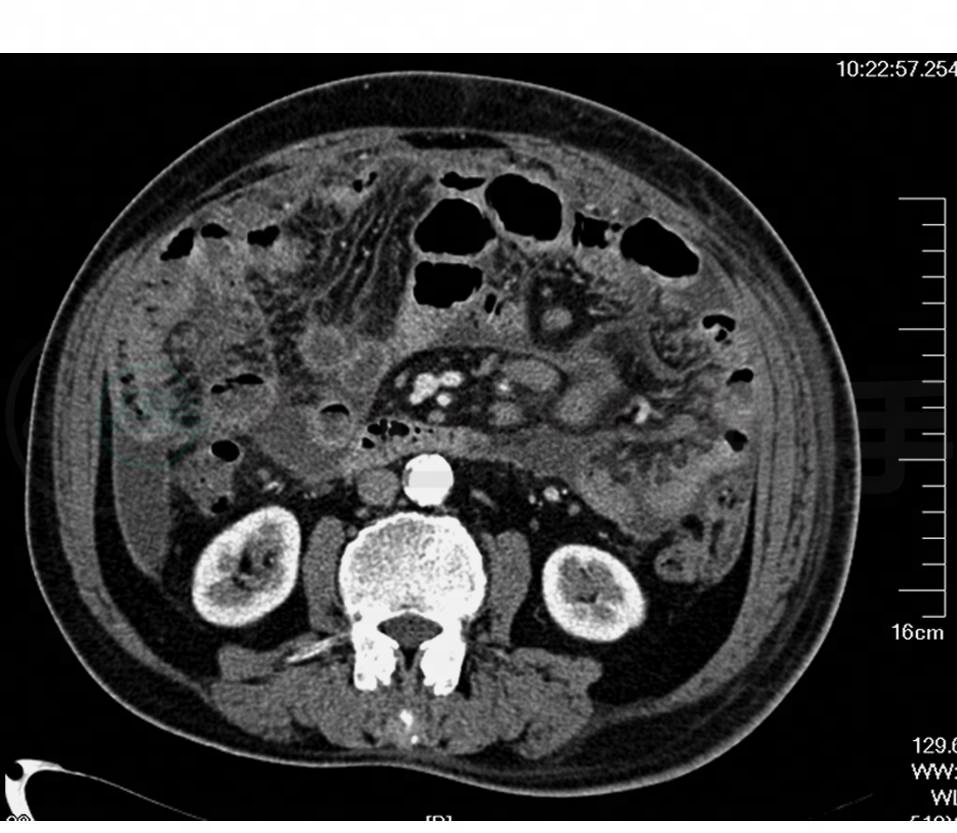

全腹部增强CT:腹腔及右心膈角区多发肿大淋巴结(图1),注意淋巴瘤可能;腹盆腔积液,右侧胸腔积液。

图1 全腹部增强CT

腹膜后及肠系膜血管束周边见多发肿大淋巴结影